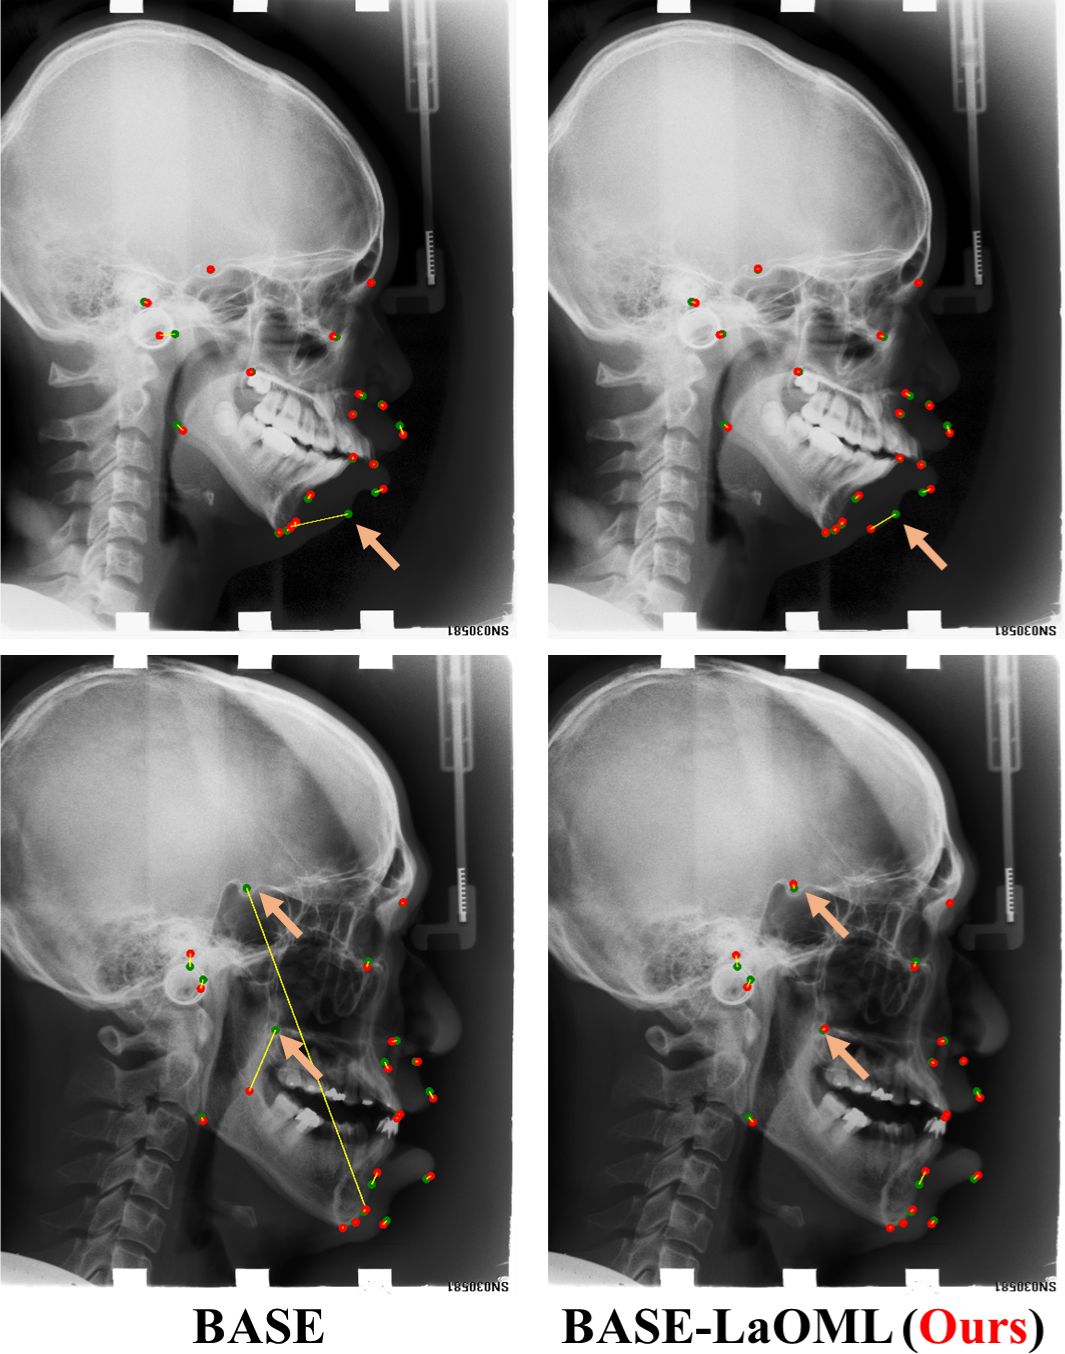

We show the results of comparing our BASE-LaOML to BASE-RNN, BASE-GAN, BASE-C, and other state-of-the-art methods on the Test2 subset of the ACXRLDC dataset in Table 2. We offer the PCK under 2 mm, 2.5 mm, 3 mm, and 4 mm threshold and the Mean (S.D.) MRE. Our baseline model obtains only a little worse result than most state-of-the-art methods, although it does not make additional network constraints. As illustrated in Fig. 7, landmarks in Cephalometric X-Ray images prefer the different to generate the heatmap ground truth. We conjecture that choosing an appropriate instead of a commonly small can improve the model. We validate this assumption in the following ablation studies by using different . Compared to the BASE, the BASE-LaOML method performs preferably in landmark localization with MRE improvement of 0.18 mm in average and 2 mm in standard deviation. When comparing with other state-of-the-art algorithms, it is clear that the average MRE for most of the other results is above 1.45mm. Also, in line with the prenatal ultrasound dataset results, the Base-C method has the worst localization performance among all the compared methods. Fig. 8 presents some examples from different patients of the ACXRLDC dataset. Most predicted landmarks correspond to the positions where they are supposed to be. Also, the results support that the proposed LaOML alleviates the extreme errors in landmarks’ localization.

In terms of PCK to evaluates the distribution of predicted landmarks around ground truth, the BASE-LaOML achieves the best performance on other metrics, although our methods are only slightly less than the results in [8] when the threshold of PCK is set to 4.0 mm. Additionally, Payer et al. [24] present results under the other arrangement by combining two test datasets. Nevertheless, the attentive feature pyramid fusion (AFPF) introduced in [8] has achieved much higher accuracy under the same configuration. These results suggested that our BASE-LaOML is more accurate in localization and the same robust to mislocalization as the AFPF [8]. Moreover, all localization improvements can be attributed to additional geometric constraints for the anatomically ill-defined landmarks, such as attention mechanism [8], local patches [35], and learnable . However, both GAN and RNN methods gain fewer improvements in comparison with other constraints methods. This can be partly explained as GAN makes the heatmap output more consistent with the prior heatmap, but it poses no localization constraints directly to reduce localization error. On the other hand, the RNN-based model might prefer a more complicated and task-specific relation among landmarks to fully explore the dependence among different landmarks, restricting the positioning accuracy.